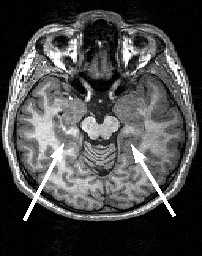

МРТ головного мозга. Аксиальный срез. Центральная борозда (стрелки).

МРТ головного мозга. Аксиальный срез на уровне крыши боковых желудочков. Центральная борозда (стрелки).